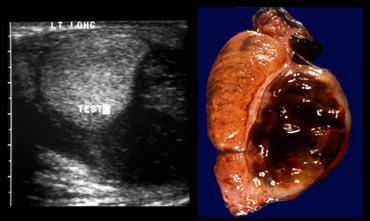

Gray scale Ultrasound

Siêu âm thang xám có giá trị hỗ trợ, không phải trong việc chẩn đoán, mà trong việc tiên lượng kết quả.

Trong 4-6 giờ đầu, cấu trúc tinh hoàn vẫn bình thường.

Trong giai đoạn này tinh hoàn vẫn có thể bảo tồn được, do đó hình ảnh bình thường trên siêu âm thang xám đồng nghĩa với tiên lượng tốt.

Sau giai đoạn này, tinh hoàn trở nên không đồng nhất và to ra trong vòng 4-24 giờ tiếp theo, mào tinh hoàn và thành bìu có thể sưng lên và giảm âm.

Hình ảnh tinh hoàn ngày càng xấu đi trên siêu âm thang xám tương quan với khả năng sống sót giảm dần (1).

Cách để nhận biết sự khác biệt về độ hồi âm là chụp ảnh cắt ngang của cả hai tinh hoàn.

Các hình ảnh bên trái cho thấy bên bị ảnh hưởng có kích thước lớn hơn và độ hồi âm cao hơn.

Tinh hoàn này có thể không còn khả năng bảo tồn.

Tinh hoàn có thể có độ hồi âm cao hơn hoặc thấp hơn, điều đó không quan trọng, miễn là có sự khác biệt thì tiên lượng sẽ xấu.